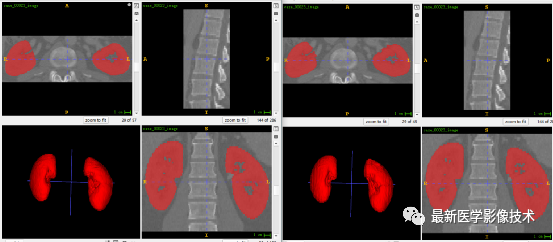

5、验证集分割结果

左图是金标准结果,右图是预测结果。